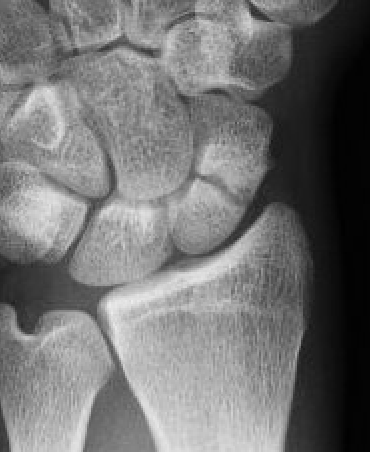

Xray

Fibrous nonunion with minimal displacement and minimal resorption

Nonunion with significant displacement and bone resorption